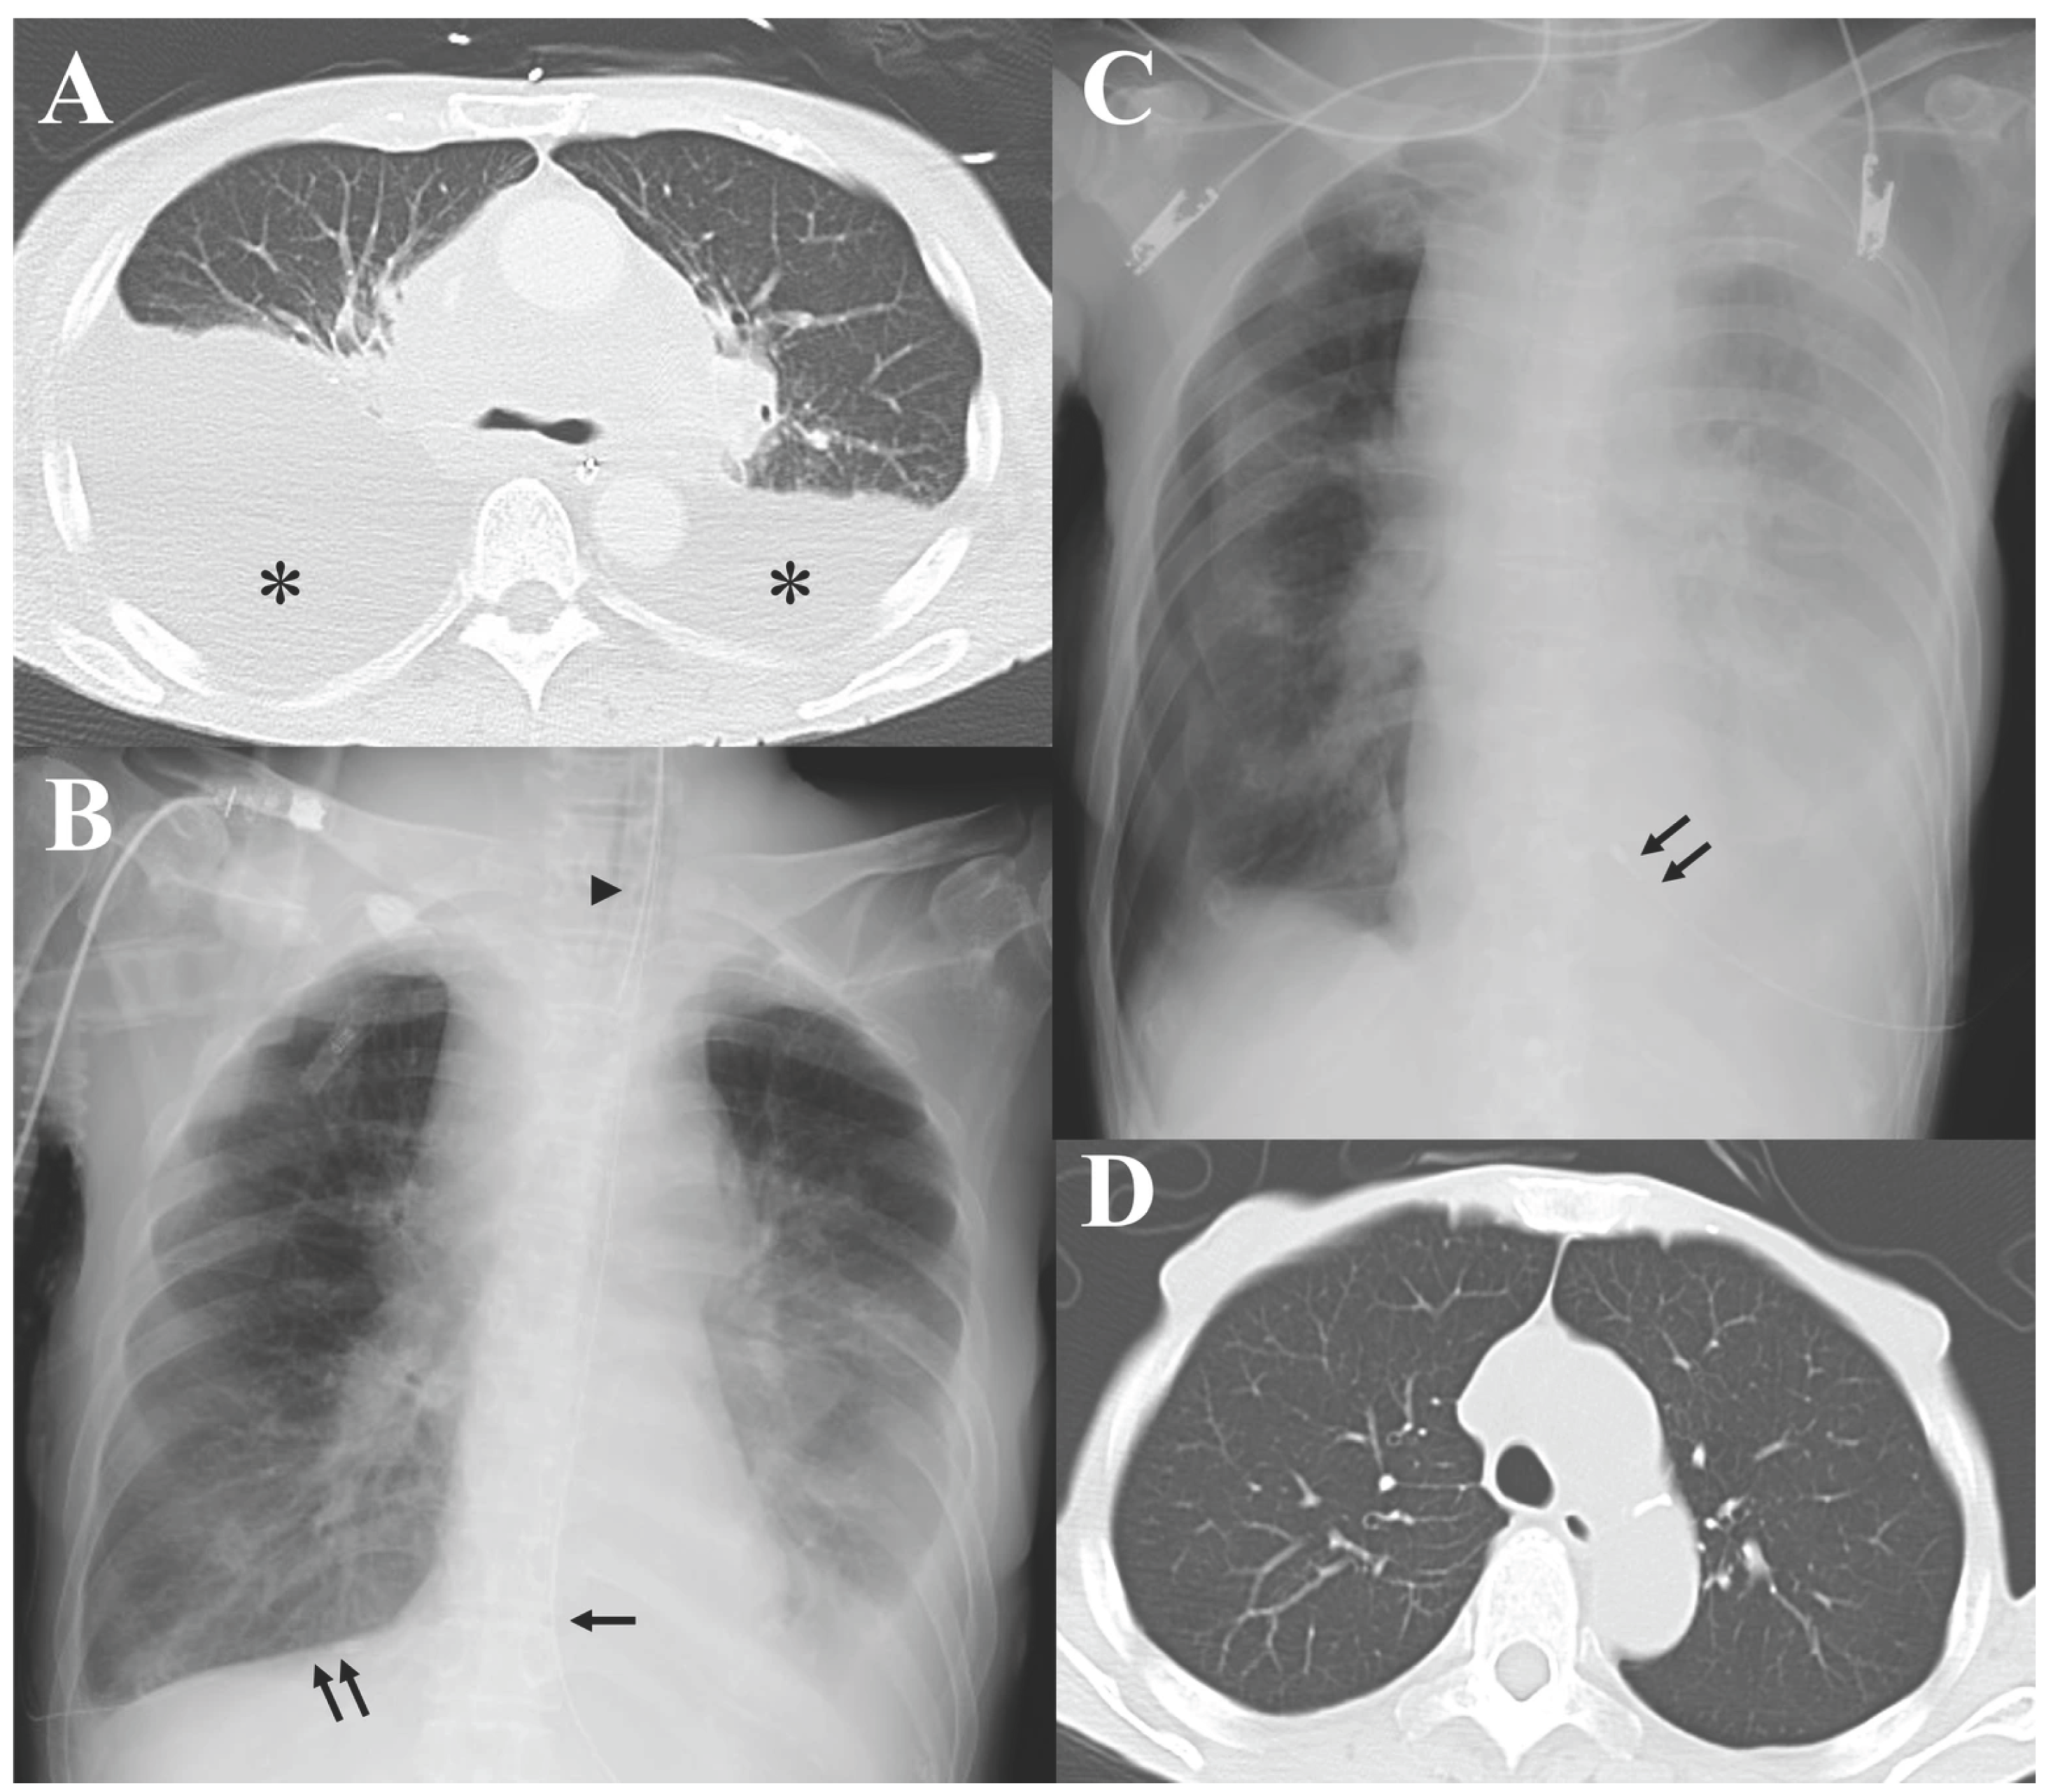

Mantle Cell Lymphoma with Persistent Massive Pleural Effusions Requiring Invasive Mechanical Ventilation and Bilateral Continuous Thoracic Drainage

2. Case Presentation